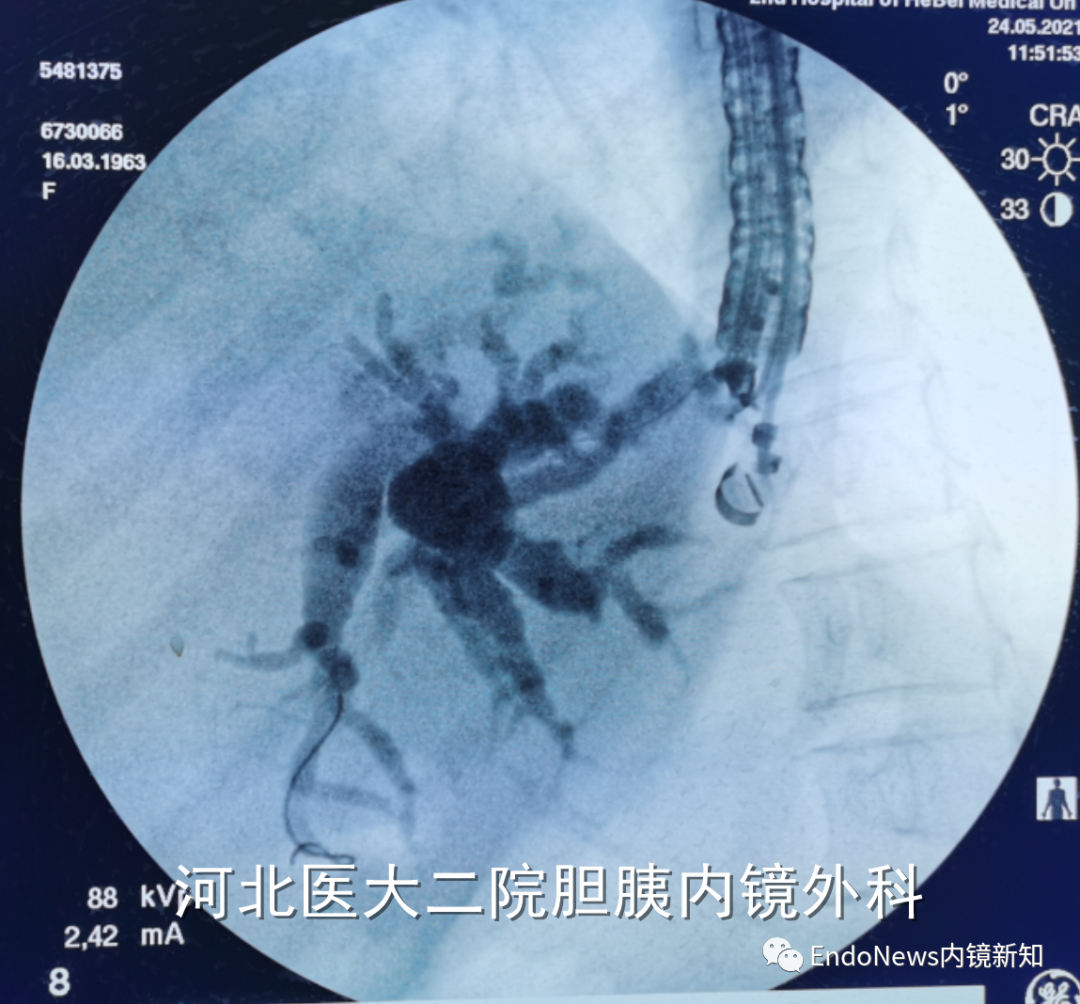

幸运的是,此患者第一针穿刺即成功,随后注射造影剂(EACP),显影后可观察到如图1(a)中所示,这个患者肝内胆管分支很多,但是由于每支均比较细,不容易找到理想的目标穿刺胆管。

下一步进入导丝之后,我们发现导丝朝向胆管上游(即肝缘方向,如图1(b)中所示),这时需要用到此前提到的调整方法:将穿刺针和导丝往回撤,尤其穿刺针,要撤入到肝实质内,但要注意导丝不能往回撤太多,这个过程一定要在X线下谨慎操作。

图1(a)